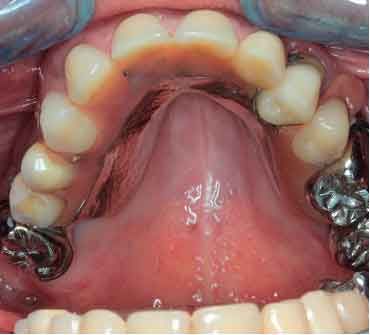

étape 1 – Scan intra-oral

Dans un flux de travail numérique , la première étape implique l'acquisition par scanner intra-oral (IOS). Cependant, dans les cas où les références sont insuffisantes, obtenir une empreinte précise peut être difficile. Découvrez une méthode alternative pour construire votre patient virtuels dynamique

Photo - Situation intra-orale